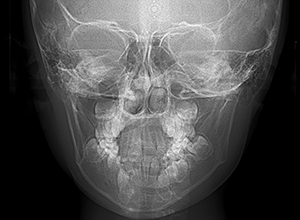

| セファロ所見 | 上下顎骨は調和のとれた位置関係を示していたが、頭蓋に対して両顎共に前方に位置していた。上下顎前歯は唇側傾斜していた。 |

| パノラマ所見 | 過剰歯抜歯後は特に問題ない。 |